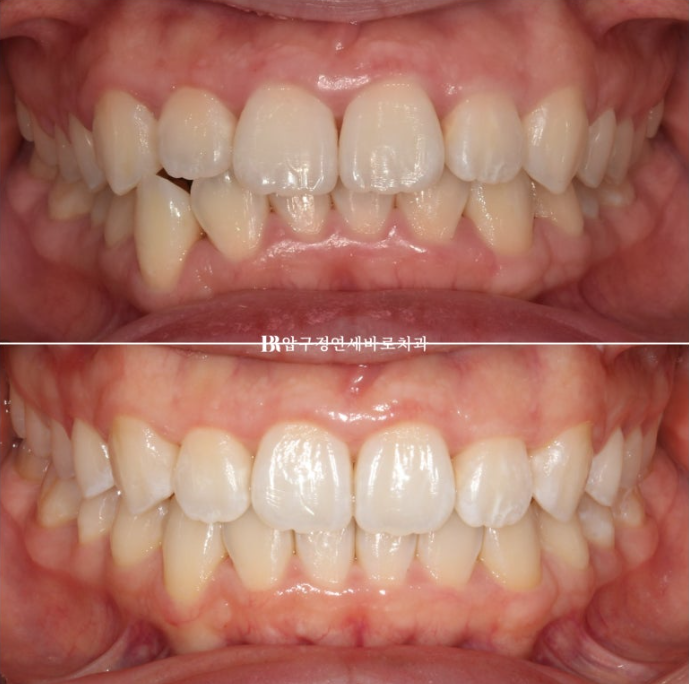

23.07

교정을 위해 내원한 환자분

윗니가 아랫니를 많이 덮어서 앞니가 깊게 물리는 과개교합이 보이고 위 아래 치아 중심선이 맞지 않습니다.

23.07-24.04

순서대로 23.07 초진 - 23.11 1차세트 후 재제작 - 24.04 치료 종료

총 치료기간은 중간에 장치 주문 후 기다리는 시간을 제외하면 실제 8개월 입니다.

치간삭제로 윗니 가운데 블랙트라이앵글도 없어졌습니다.